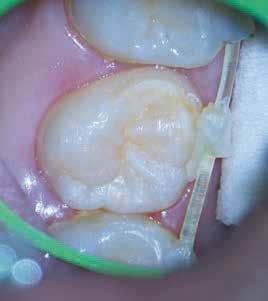

Krell és Caplan kutatásában 2086 repedt fogat vizsgáltak meg. A vizsgált fogak között leggyakrabban a második alsó nagyőrlőfogak (36%), majd ezt követően az első alsó nagyőrlők (27%), és végül az első felső nagyőrlők (18%) fordultak elő. A kutatási eredményeik szerint a fogbél állapota nem befolyásolta jelentős mértékben a kezelés várható kimenetelét. (Irreverzibilis pulpitis 85%; necrosis 80%; korábban gyökérkezelt 74%). A kimenetel szempontjából ugyanígy indifferens volt a páciensek neme, életkora, a kezelés időpontja, a fog pozíciója, a fog helyreállítása során használt anyag típusa, valamint az érintett fogfelszínek száma. 2014 júliusában egy 45 éves hölgy páciens azzal a panasszal kereste fel a rendelőnket, hogy nagyjából 10 napja egy fájdalmas duzzanat alakult ki a jobb felső első kisőrlője koronája mellett (14). A klinikai vizsgálat során egy amalgámtömést találtunk a panaszos fogban. A tömés széli zárása nem volt megfelelő, a disztális záróléc és a tömés között rést tapasztaltunk. A fog disztobukkális és linguális felszíne mellett 8 mm-es csontos tasakokat mértünk. A periapikális felvételen az 14-es foggyökér disztális felszínének megfelelően vertikális irányú radiolucens felritkulást észleltünk. A klinikai vizsgálat során a mesiális zárólécet kettéválasztó törésvonalat detektáltunk (17–18. ábra). A fogszenzibilitás vizsgálata során negatív eredményt kaptunk. A páciensnek ismertettük az elérhető terápiás lehetőségeket: 1, a 14-es fog eltávolítása, majd a foghiány 3 tagú cementezett híddal történő pótlása; 2, a 14-es fog eltávolítása, kemény- és lágyszöveti augmentáció, majd implantátum behelyezése; 3, a 14-es fog gyökérkezelése, gyökértömése és ezt követően a csücsökborítást biztosító restaurátum készítése. Arra is felhívtuk a páciens figyelmét, hogy a 3. terápiás lehetőség választása esetén nem tudjuk a fogmegtartás sikerességét garantálni, de végül – főként anyagi okok miatt – mégis ezt a terápiás opciót választotta. Fontos megjegyezni, hogy a repedt fogak ellátási lehetőségeit a törésvonal mélysége, elhelyezkedése, lefutása nagyban befolyásolja. A kezelés megtervezése során a fog és a fogat körülvevő szövetek állapotával kapcsolatos számtalan különböző faktort kell egyidejűleg figyelembe vennünk. A gyökérkezelést követően a gyökértömést meleg vertikális kondenzációs technikai alkalmazásával készítettük el (19. ábra). A hozzáférési nyílást folyékony és hibrid kompozit tömőanyag segítségével zártuk. A zárás elkészítése során a dr. David Clark által kifejlesztett Bioclear matricarendszert alkalmaztuk. A 6 éves kontroll során készített (2020) röntgenfelvételen a csontos defektus telődése volt megfigyelhető. Ez is a parodontális defektus gyógyulását igazolta (20–21. ábra).